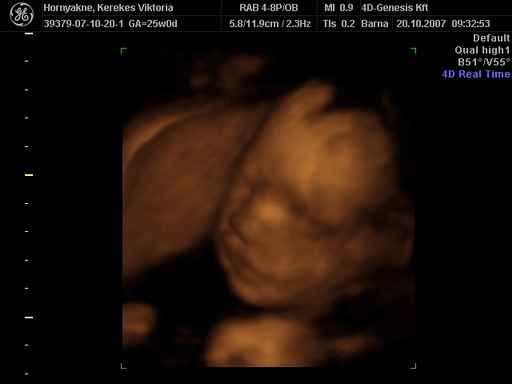

A tegnapi 4D-n már megmutatta magát ez a kis cukorfalat. Majd teszek fel képeket.

Várjuk a képeket a 4D-ről. A szerdai doki vizsgálaton mindent rendben találta: méhszáj teljesen zárt, viszont a folyásra felírt hüvelykúpot. A pénteki vidéki 4D sajna megint nem sikerült olyan jól, megint úgy feküdt, viszont ott is minden rendben volt: néztek köldökzsinór áramlást és az is teljesen OKÉ volt. :lol:

A kép amit fényképezett a doki nagyon homályos lett, így sajna csak a múltkori képeim vannak fenn, szerintem ezeket már feltettem (mármint a linket), de azért ide is becsatolom:

Kép

Jó sokat írtatok. Na most viszont teszek fel képet.

Íme:

Remélem jól látszik, hogy kisfiú lesz. :lol: